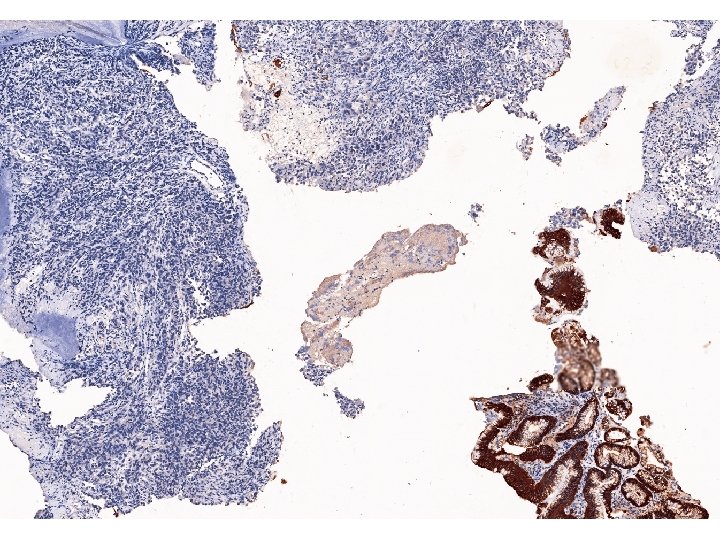

Imunohistologický nález nádorových buněk • K vyloučení nediferencovaného karcinomu vyšetřeny cytokeratiny, skupinovitě (AE 1/AE

Imunohistologický nález nádorových buněk • K vyloučení nediferencovaného karcinomu vyšetřeny cytokeratiny, skupinovitě (AE 1/AE 3), i jednotlivě, reakce nádorových buněk bylanegativní. • Také reakce na CD 117 na možný stromálmí nádor byla negativní. • Reakce na S 100 protein byla slabá, ale zřetelně pozitivní, silně pozitivní reakce byla na Melan A i na HMB 45.